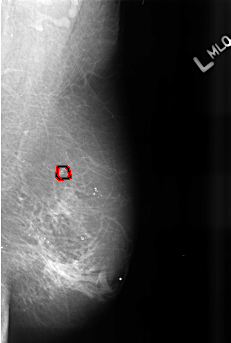

B_3472_1.LEFT_MLO

FILE: B_3472_1.LEFT_MLO.OVERLAY

TOTAL_ABNORMALITIES 1

ABNORMALITY 1

LESION_TYPE CALCIFICATION TYPE PLEOMORPHIC DISTRIBUTION CLUSTERED

ASSESSMENT 4

SUBTLETY 3

PATHOLOGY BENIGN

TOTAL_OUTLINES 1

BOUNDARY